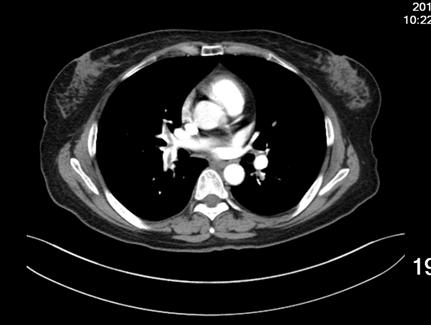

患者女性,52岁,因右膝关节疼痛,活动受限三十年入院。既往无高血压等慢性病史,无静脉血栓栓塞症病史,无慢性静脉瓣功能不全病史。诊断:右膝半月板损伤,骨关节炎。术前排除手术禁忌,于CSEA下行右膝关节镜下探查清理,半月板成形术。手术过程顺利,手术使用止血带,手术时间25分钟,失血约10ml。术后24小时患者下床后出现头晕、头迷、气短、冷汗、扶墙晕倒于墙边,给予心电血氧监护,血压:78/45mmHg,心率:118次/分,指脉血氧饱和度:78%,急检指尖血糖:6.4,血浆D-二聚体:1247ug/L,心肌酶谱及肌钙蛋白未见明显异常,术后2天夜晚再次出现头晕,头迷,气短,冷汗等症状,给予吸氧等治疗后症状缓解,检查肺增强CT(图1),示患者多发肺动脉栓塞,行双下肢静脉彩超检查,示右小腿肌间血栓,左小腿肌间静脉扩张(图2)。术后第3天于局麻下行经皮下腔静脉滤器置入术后,转入呼吸科行继续治疗。

1增强肺动脉CT:多发性肺动脉栓塞。